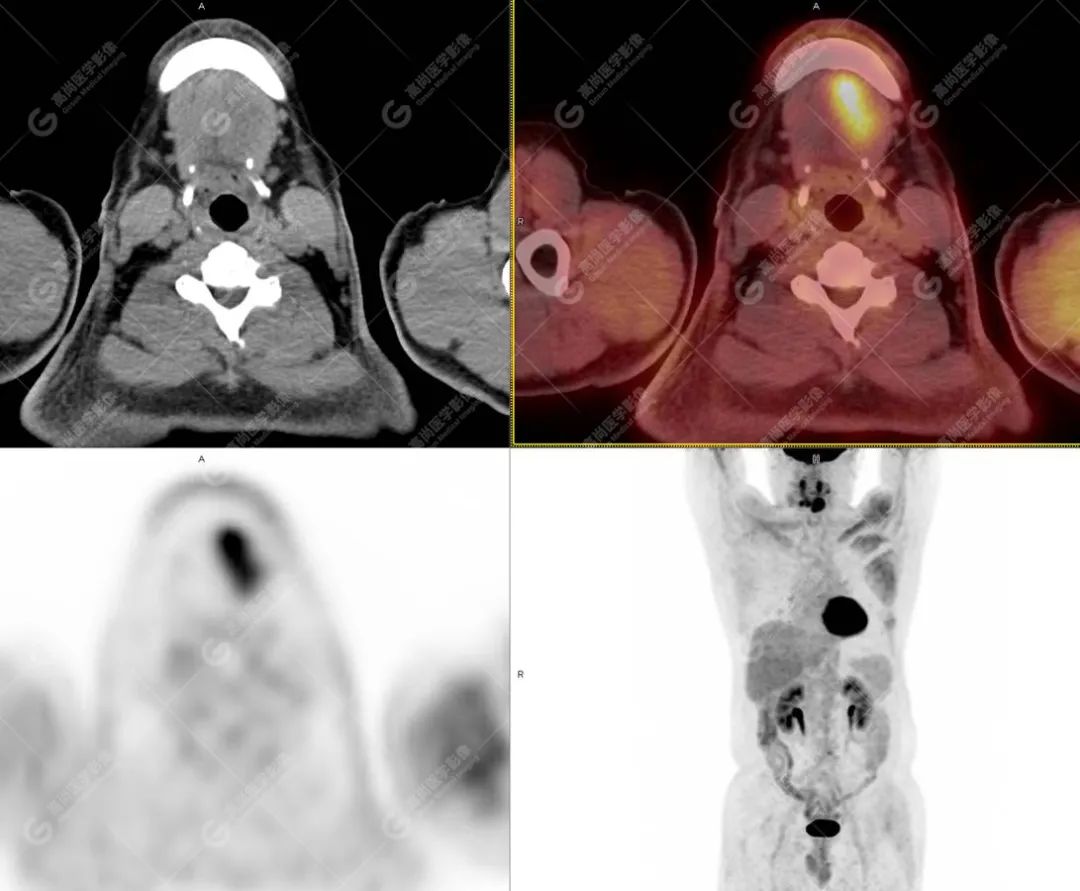

PET/CT影像图

图4

影像诊断: 1.舌体部左右侧软组织明显增厚,密度稍低,左侧为著,代谢异常增高, 考虑为舌癌,并口底受侵, 建议穿刺病理学检查明确。

2.双肺多发大小不等实性结节,部分代谢轻度增高, 考虑为转移瘤。

影像表现: 口底浸润性、 边界不清楚的混杂密度肿块,增强不均匀强化;舌中隔偏曲;肿块邻近口底脂肪间隙消失,病变与邻近肌肉、血管分界不清,可包埋血管,可有颈部淋巴结肿大。